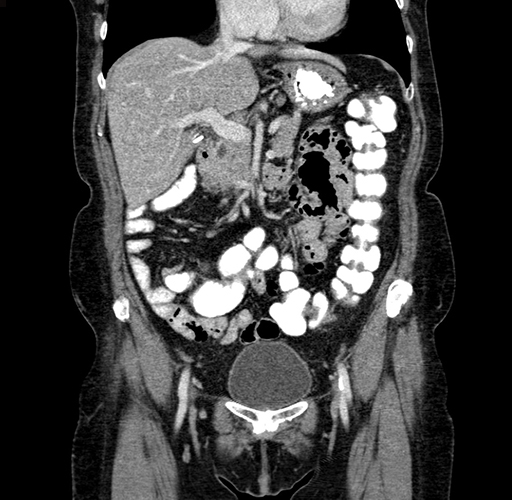

Pre-Chemo: Coronal Venous

Coronal Venous